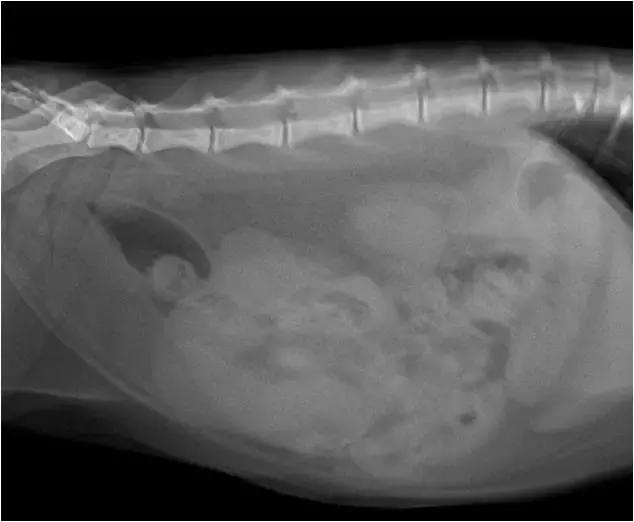

猫咪小妹送至医院时已较为消瘦虚弱

检查发现其下腹部触诊有坚实样游离物体

1、 患病猫咪子肚子会胀大并且紧绷。

(三个月以来猫咪小妹无孕腹部却不断变大)

阴门湿润,触诊腹部可感到子宫角增粗

猫咪小妹在福懋宠物医院接受治疗

纠正脱水及电解质平衡

并以抗生素加以治疗,获得了相当的疗效

除此之外还进行外科手术

将已感染的卵巢和子宫一并切除